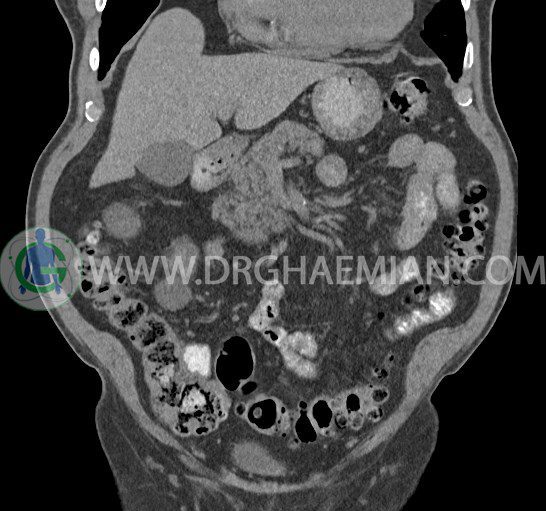

سی تی اسکن لگن یکی از روش های تصویربرداری با سی تی اسکن است. این روش با استفاده از تشعشعات تصاویر عرضی از ناحیه شکمی ایجاد میکند. در این کیس ديورتيكولوزيس، کیست های کورتیکال در هر دو کلیه، لنفادنوپاتی، کلسیفیکاسیون دیواره آئورت و شریان ایلیاک، تغییرات DJD ناحیه توراکولومبار و پروستات بزرگتر از عادی دیده می شود.

در سي تي اسکن اسپيرال شکم و لگن با و بدون کنتراست خوراکی و وريدی (مولتي ديدکتور 16 با مقاطع ظريف و بازسازي هاي ساژيتال و کرونال):

– کيست هاي کورتيکال ساده به قطر 5 mm تا 50 mm در کليه راست و به قطر 5mm تا 55 mm در کليه چپ

– توده ايزودنس به ابعاد mm 17 x 28 در پره ائورت مجاور قسمت تحتاني D3 دئودنوم مطرح کننده لنفادنوپاتي و با احتمال کمتر آنوريسم ترومبوزه (نيازمند مطابقت سونولوژيک)

– کلسيفيکاسيون ديواره آئورت و شريان ها ايلياک همراه با نشانه هاي ترومبوز مورال در بيفورکاسيون ائورت با امتداد به پروگزيمال هاي شريان هاي ايلياک

– ديورتيكولوزيس در کولون نزولي وسيگموئيد

لنفادنوپاتي به ابعاد mm 22 x 25 مجاور شريان ايلياک خارجي چپ و به ابعاد mm 17 x 28 مجاور شريان ايلياک خارجي راست

– تغييرات DJD در ناحيه توراکولومبار و

– پروستات به ابعاد mm 45 x 54، بزرگ تر از نرمال

مشهود است.